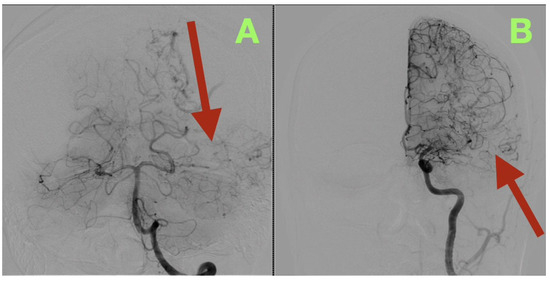

Background/Objectives: Arteriovenous malformations (AVMs) in the dominant temporo-parieto-occipital (TPO) junction of the brain are extremely rare and very difficult to remove surgically because this area includes multiple sensory and language networks. Due to the fact that many patients present with bleeding, surgeons have to find a delicate balance between removing all of the AVM tissue and preserving the functional areas of the brain where important functions occur. This study is reporting a case demonstrating how precise clinical–radiologic correlation, detailed anatomical knowledge, and deliberate microsurgical techniques can allow safe removal of the AVM and improve the patient’s neurologic function without the need for additional intraoperative technology. Case Presentation: A 47-year-old right-handed male patient experienced persistent neurological deficits after experiencing a hemorrhage from an AVM in his dominant posterior hemisphere, which included mild language difficulties, right hemifacial–brachial spasticity, parietal sensory loss and a visual field defect of his right eye known as an inferior quadrantanopia localized to the TPO junction. Cerebral angiography identified a small, compact, high-flow AVM (40 × 30 mm) fed by distal branches of the middle cerebral artery (M4), posterior cerebral artery (P4), anterior cerebral artery (A4), as well as a small branch of the superior cerebellar artery (SCA). Blood drained into two veins of the Trolard and Labbé. The authors removed the AVM completely by circumferential dissection of the nidus along gliotic planes using a microscope. Feeders were then sequentially disconnected, and the venous outflow was preserved until the AVM could be removed en bloc. Post-operative angiograms demonstrated complete removal of the AVM with normalization of blood flow to the surrounding cortex. The patient’s neurologic function improved over time and at three months post-operatively, he was functioning independently (modified Rankin Scale = 1; Barthel Index = 100) and there was no evidence of residual nidus or edema on imaging. Conclusions: High-flow AVMs in the dominant TPO junction can be completely removed using a disciplined microsurgical approach and a feeder first/vein last disconnection method based on anatomy. The patient’s improvement in function represented reperfusion and reintegration of an injured but still functional network of the brain, reinforcing the idea that careful observation, a deep understanding of brain anatomy, and restrained surgical technique are critical to achieving long-term results in AVM surgery. Full article

Figure 1